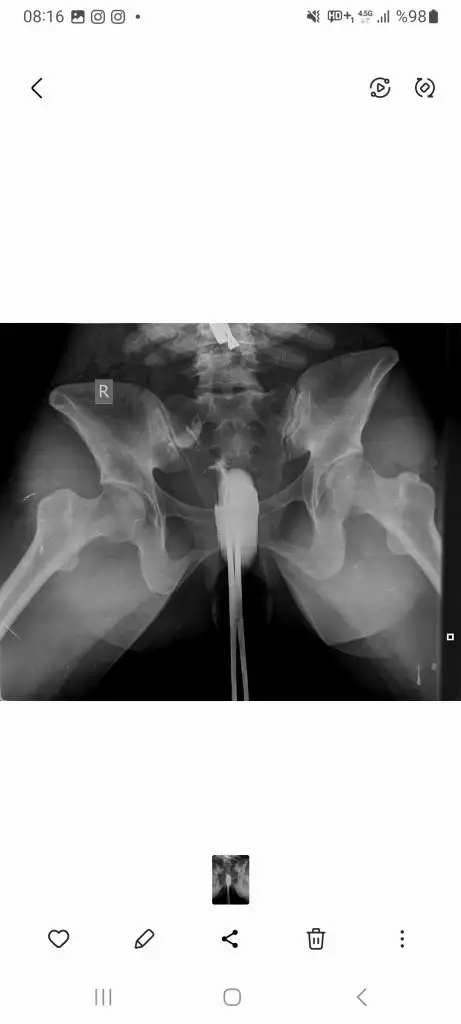

Siliklesmis gorunuyor benceKızlar yine ben ahaha sizce çatlamış mı bugün ne diyorsunuz? 1. Foto dün 2. Foto bugün